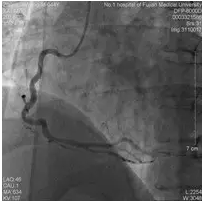

第一次手术过程

手术时间:2014年7月25日下午1点50分。

术中用药:术中追加肝素2000单位。

手术过程:右冠中段闭塞。

![]()

右冠植入Partner支架3.0×24 mm。